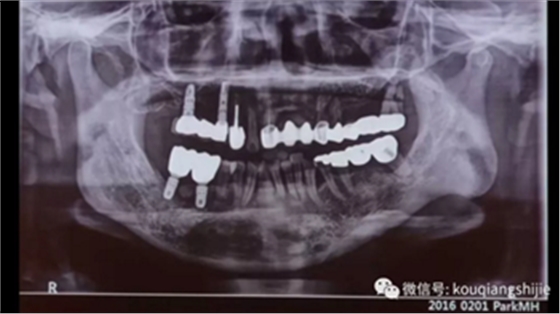

这是另一个患者

我们可以看到#23的颊侧骨壁基本已经破坏没了

从CT上我们也可以看到腭侧形成非常厚的黏膜

拔牙后我们可以看到这部位的骨缺损非常严重,需要大量的骨增量和黏膜增量。

我们将覆盖在拔牙创的线性黏膜组织拉上来,在黏膜与骨之间形成充分的修复空间。

术后恢复情况

当黏膜组织愈合良好之后,再进行进一步种植,并对不足的部分进行进一步修整。